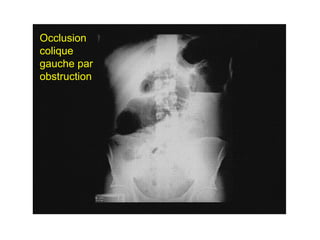

Occlusion

colique

gauche par

obstruction

Occlusion colique

Niveaux hydroaériques périphériques, plus hauts que larges